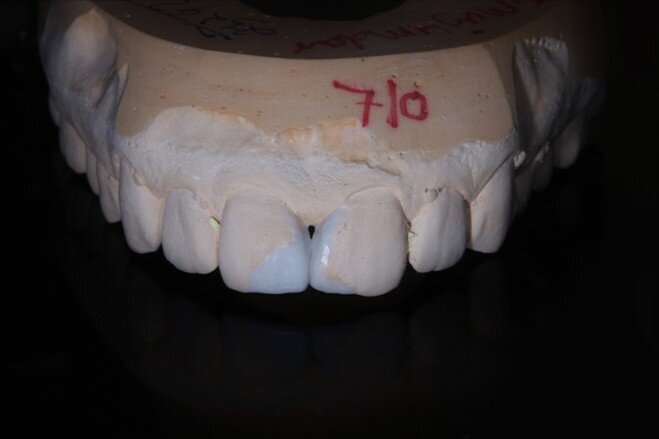

Two weeks later, the shade [ Fig 3 ] stabilized and the teeth were ready for bonding. We observed that the central incisors were still darker than the neighboring teeth. Direct composite veneers were planned with the help of a lab made wax up [ Fig 4 ] and a putty index. Bevels were placed and most of the preparation was in enamel. After the total etch protocol, 5th generation bonding agent was used. 3M Z350XT shades were used for the build up. A2 Enamel shade was used for the palatal shell [ Fig 6 ] and the proximal walls [ Fig 11 ].

Fig 6 Enamel shade for palatal shell on putty index